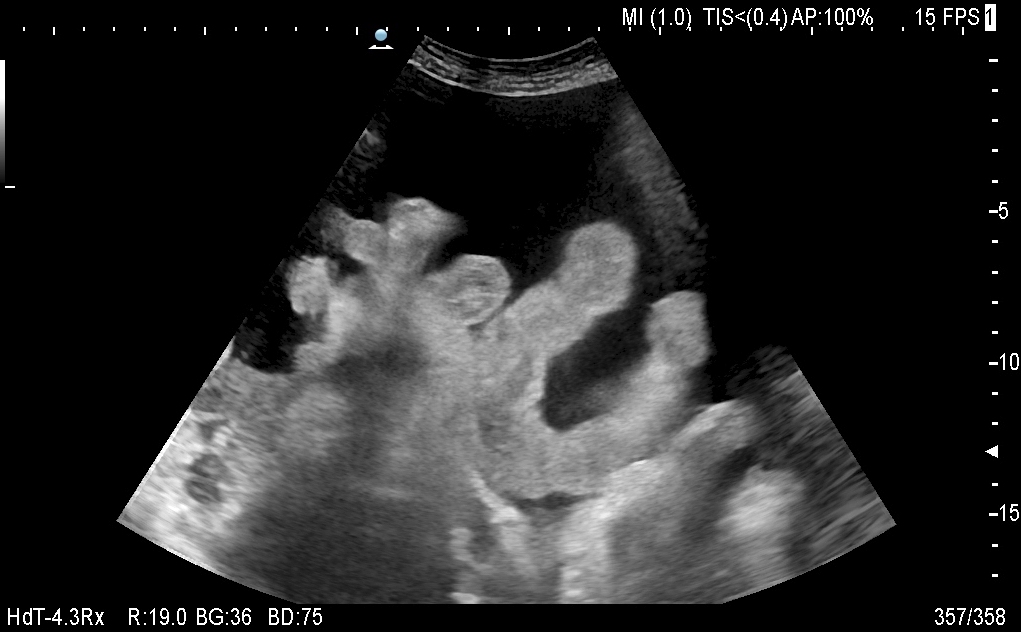

Реальный асцит